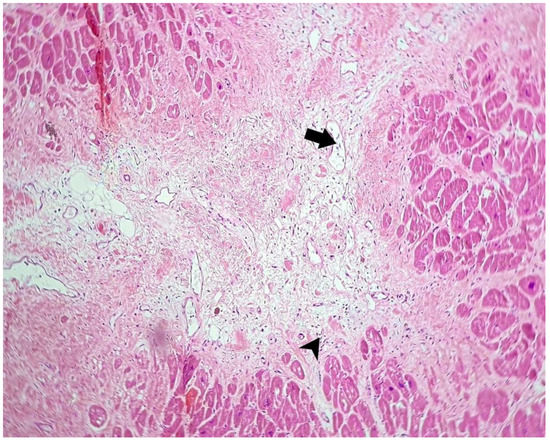

- Areas of undulated and/or fragmented myocardial fibers, with eosinophilia and nuclear pyknosis with or without enucleation of the myocytes: nine cases

- In one case (with positivity for SARS-CoV-2 antibody), we observed a large area of myocardial necrosis with enucleated muscle fibers, eosinophilia, extravasated erythrocytes, scattered lymphocytes, neutrophils, and necrotic debris, with a halo of granulation tissue composed of newly formed capillaries, macrophages, and lymphocytic infiltrate.

| Case no. 6 | Rich diffuse inflammatory lymphocytic infiltrate in the subepicardial space visceral pericardium, with focal fibrin deposits on the surface Large extended areas of fibrosis interposed between myocardial fibers, sequestrating groups or individual myocytes, with thick, poorly cellularized, horizontally-arranged collagen fibers. In these patches of fibrosis, there is a more myxoid appearance, with an increased number of blood vessels and with a perivascular scattered lymphocytic infiltrate Small, poorly-defined areas of myocardial fibers with cytoplasmic vacuolation, nuclear pyknosis, apoptosis, and necrotic debris between these fibers Undamaged myocytes near the fibrotic patches suffered nuclear enlargement, with irregular borders and granular fine dispersed chromatin, a sign of cellular suffering Severe atherosclerosis of the coronary arteries with secondary subocclusion Large area of myocardial necrosis with enucleated muscle fibers, eosinophilia, extravasated erythrocytes, scattered lymphocytes and neutrophils and necrotic debris, with a halo of granulation tissue composed of newly-formed capillaries, macrophages, and lymphocytic infiltrate |